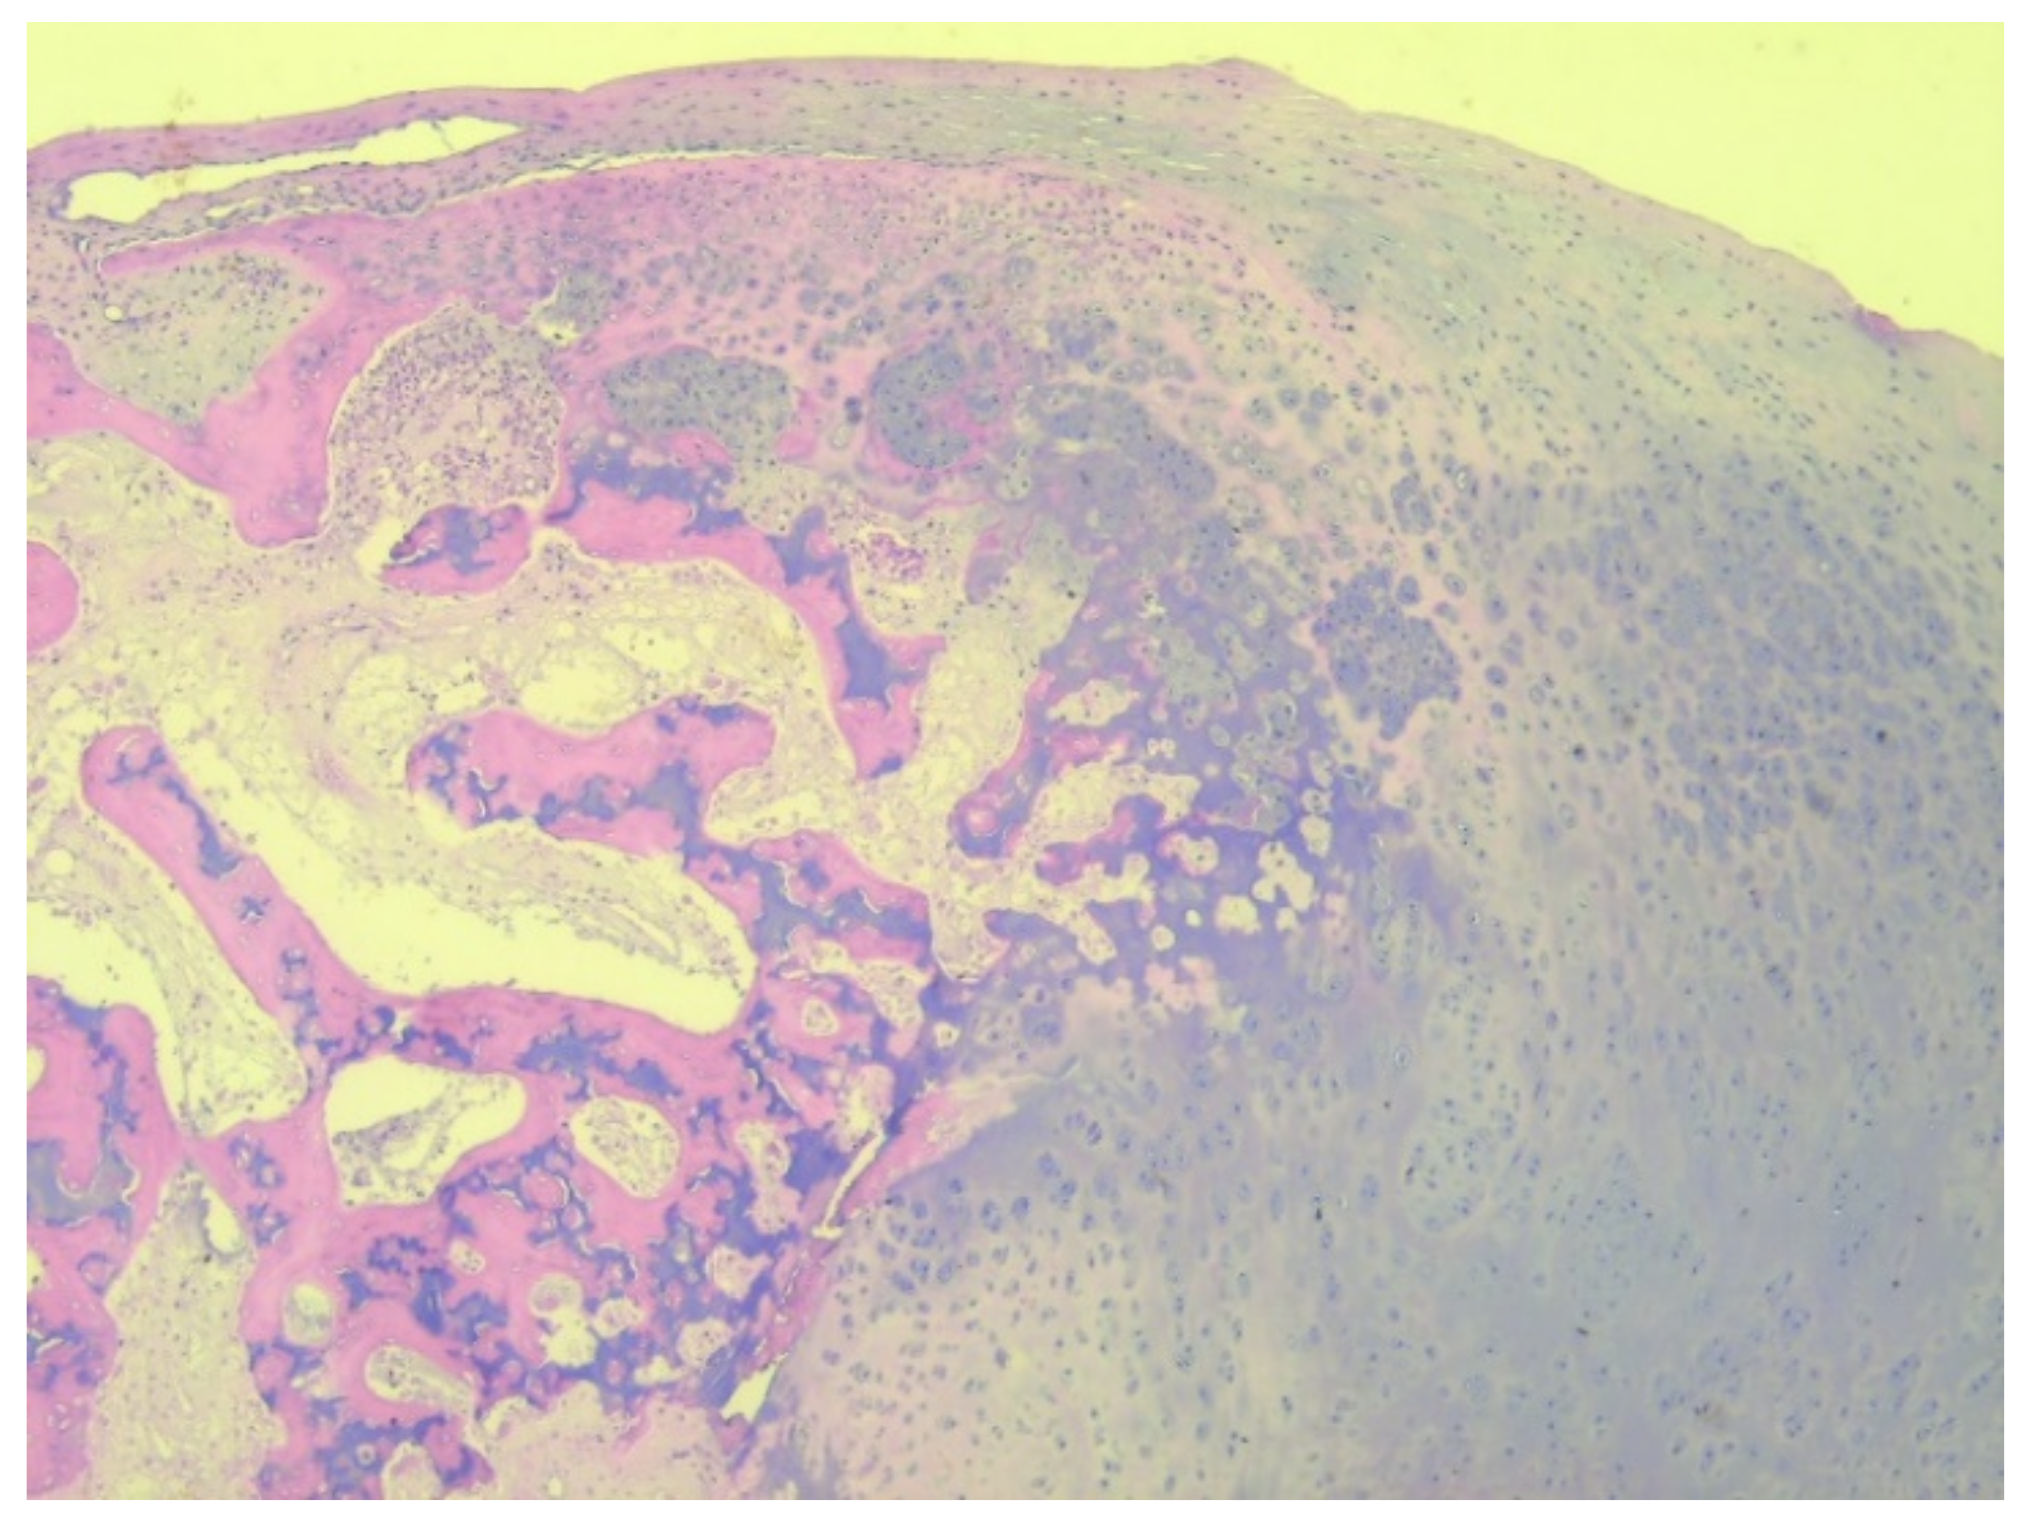

A total of eight tissue fragments, between 0.5 and 3 cm in diameter, were sent for anatomopathological diagnosis. The macroscopic appearance of the tumoral fragments was a nodular polylobate solid mass. On the slide, the top of the tumor was covered by a blue-like cartilaginous cap about 0.1–0.6 cm in width. After decalcification and preparation of formalin-fixed paraffin-embedded tissue blocks the specimen was evaluated. The result indicated tissue fragments made of bone, showing chondroid proliferation on the surface, with minimal cellular atypia, with disorganized distribution and limited columnar pattern at the basal level, slightly increased cellular density, and endochondral ossification with mineralization areas (Figure 9, Figure 10, Figure 11 and Figure 12). Fibroconnective tissue was observed on the surface of chondroid proliferation (perichondrium). The result was indicative for a benign osteochondromatous structure displaying clusters of proliferative chondrocytes in a fibrillary matrix with small ossification centers and small amounts of unabsorbed calcified cartilage. Trabecular bone was covered by an irregular cartilaginous cap.

Figure 9. Irregular and disorganized clusters of mature chondrocytes, HE, 50×.

Figure 12. Irregular clusters of chondrocytes, ossification centers, and small amounts of unabsorbed cartilage, HE, 50×.